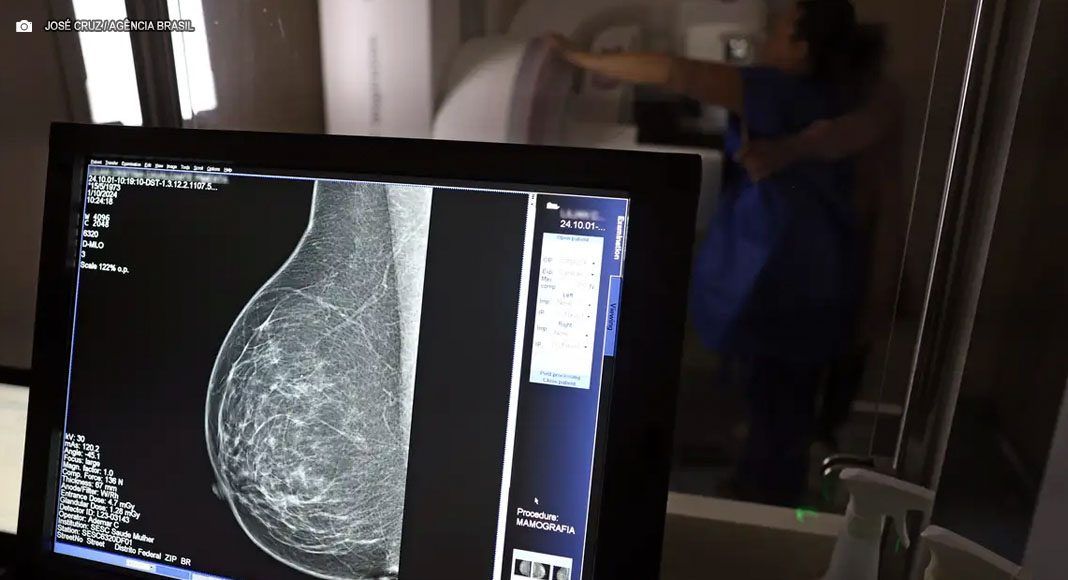

Pacientes em tratamento de câncer de mama, doença com estimativa de 73.610 novos casos no Brasil este ano, têm direito (25/Out) a benefícios previdenciários para garantir a segurança financeira durante o tratamento. Especialistas da Ordem dos Advogados do Brasil do Rio de Janeiro (OAB-RJ) detalham que, para o auxílio por incapacidade (auxílio-doença), aposentadoria por incapacidade permanente e o Benefício de Prestação Continuada (BPC/LOAS), a legislação garante condições especiais, como a dispensa de carência.

O Instituto Nacional de Câncer (Inca) aponta o câncer de mama como o que mais mata mulheres no Brasil. A advogada Danielle Guimarães, vice-presidente da Comissão de Previdência Social Pública da OAB-RJ, destaca que a doença impacta não apenas a saúde física e emocional, mas também a capacidade de trabalho das pacientes.